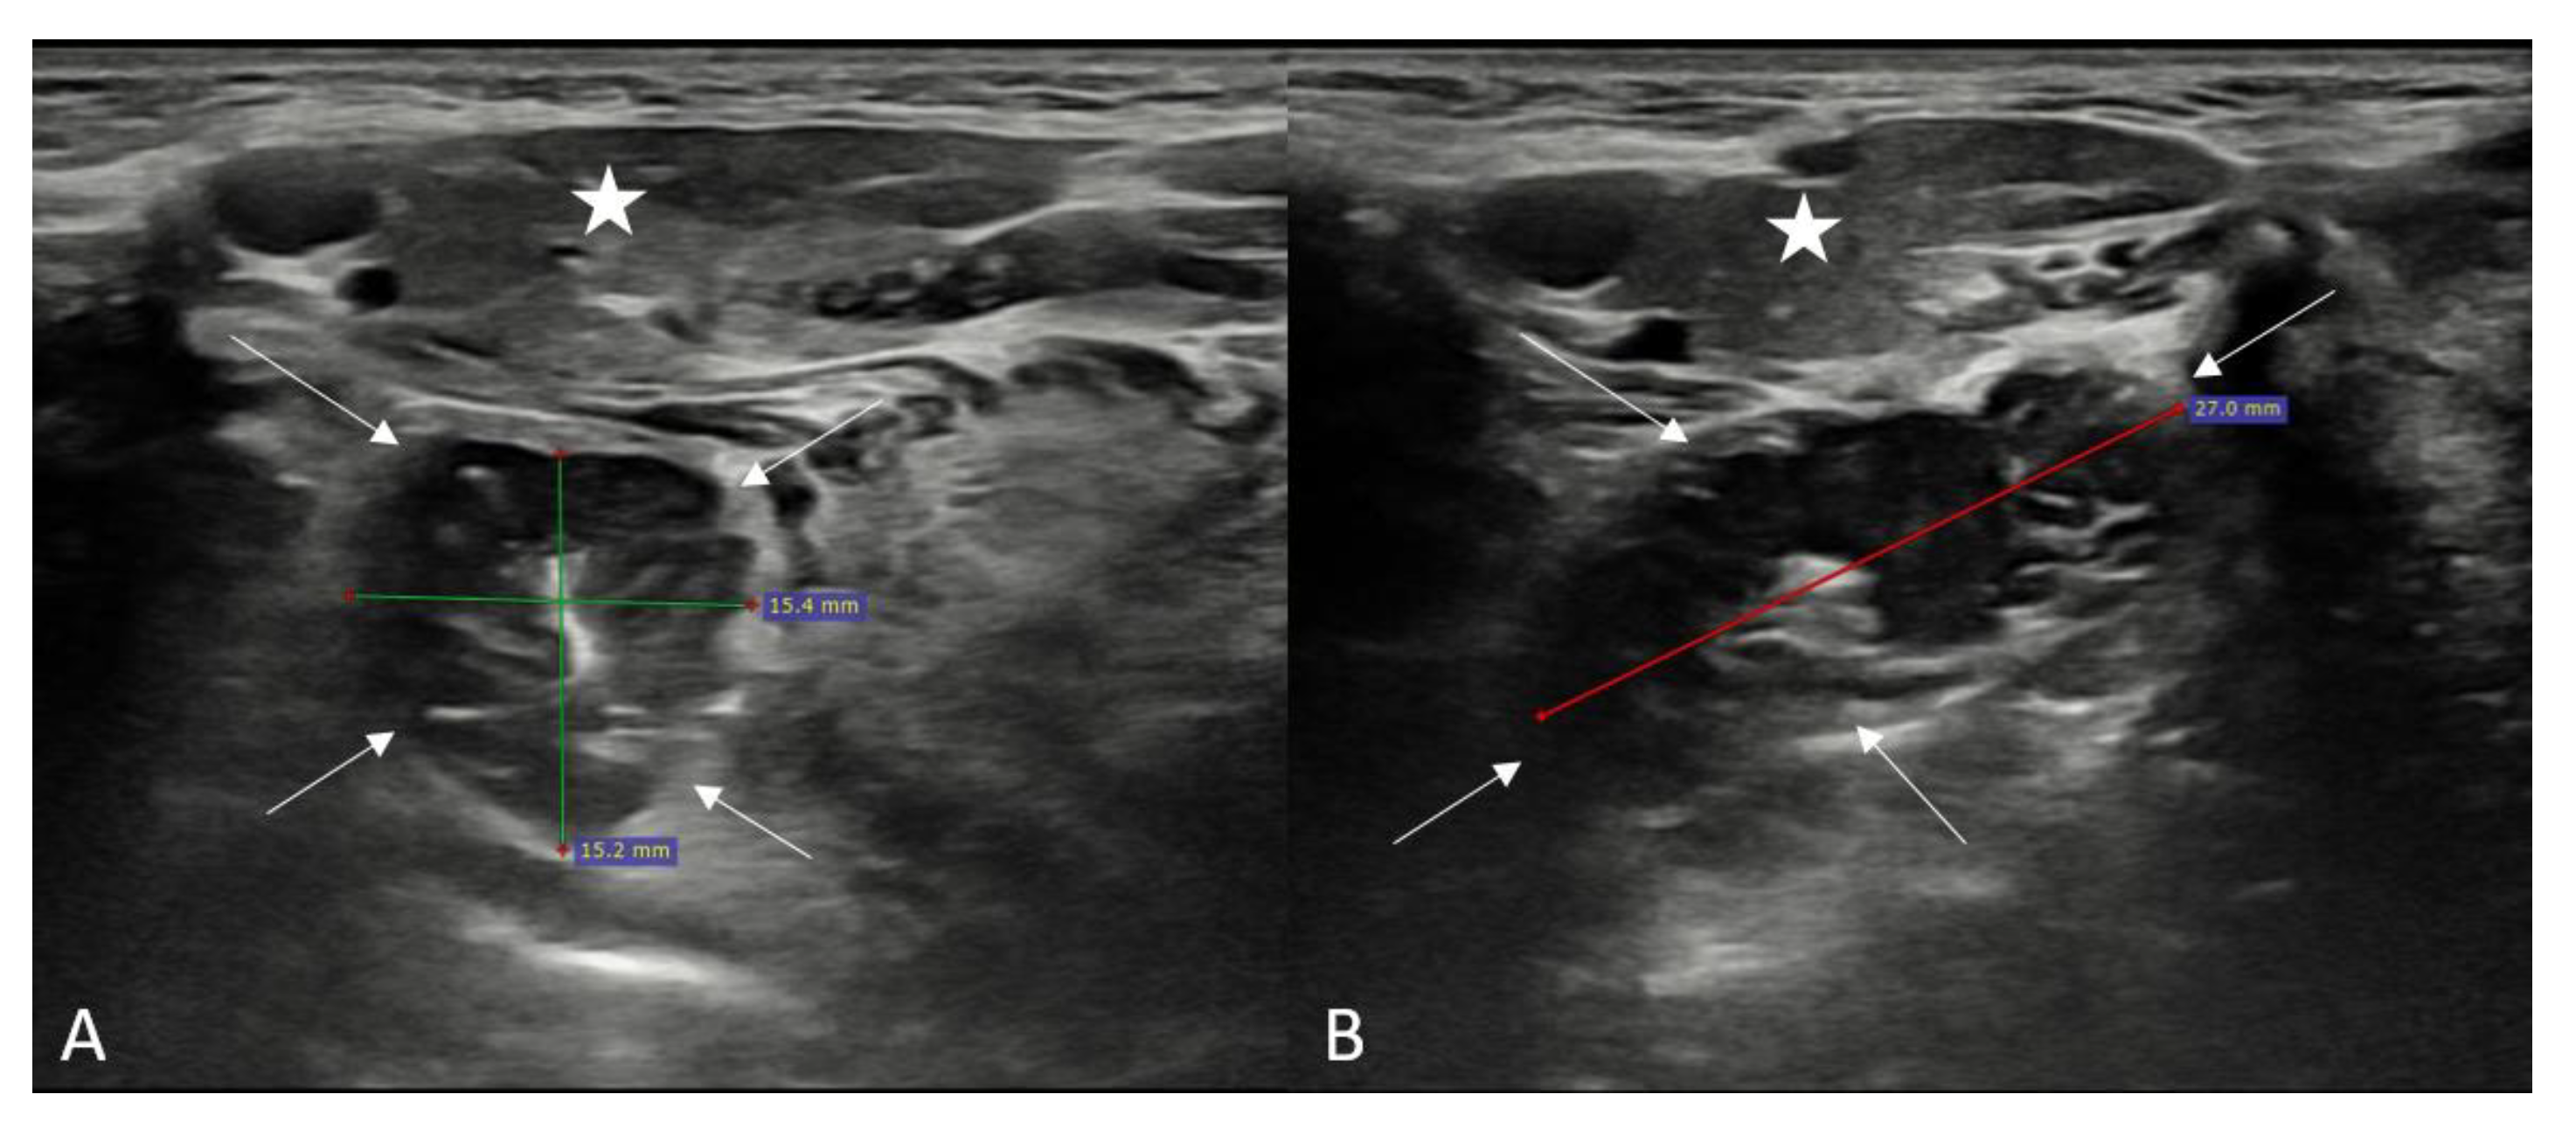

First the submandibular gland was discovered, then the palatine tonsil was visualized as a well-circumscribed hypoechoic structure just deep within the submandibular gland. Longitudinal and transverse plane imaging was performed according to the extension of the tonsil. During the ultrasound, the practitioner sometimes asked the patient to swallow to observe the movement of the tonsils. The diameters of both the right and left tonsils were measured in the anteroposterior, transverse, and longitudinal planes (Figure 1).

Figure 1.

Ultrasonographic evaluation and measurements of the palatine tonsil in a healthy participant (Asterisk: Submandibular gland, Arrows: Palatine tonsil). (A): Transverse plane, (B): Longitudinal plane.